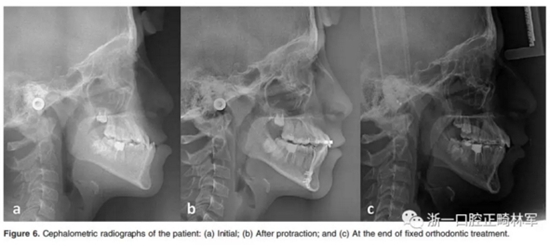

在開合關(guān)閉后,并用直絲弓技術(shù)繼續(xù)治療。在固定正畸治療過程中,有5位患者拔除上頜前磨牙,以解除擁擠和II類尖牙關(guān)系。對于正在生長發(fā)育的III類患者夜間佩戴bianator。治療前后拍攝頭顱側(cè)位片。Figure 5和Figure 6顯示了該組中的一名患者的治療過程。

觀察、牽引、正畸治療的時間分別為5.36±1.48個月,3.85±1.12個月和23.13±7.03個月。Table 1和Table 2列出了頭影測量的數(shù)據(jù)。Table 3和Table 4顯示了三個時期的差異以及這些時期的統(tǒng)計比較。在觀察期間,矢狀面骨骼參數(shù)無顯著變化。在牽引階段,A點向前運動3.59±1.32 mm(P<0.01),B點向后運動為1.85±1.46 mm(P<0.01)。上頜骨和下頜骨的骨骼變化導致ANB顯著改善(-4.18±1.47°,P <0.01,見Table 3)。固定正畸治療期間矢狀面骨參數(shù)沒有明顯變化。

關(guān)于垂直參數(shù),在觀察期間沒有觀察到顯著變化。在牽引期間,SN-UOP角度(8.28±4.41°,P<0.01)顯著下降,在固定正畸治療后其又明顯上升(- 4.51±6.19.75mm; P <0.01)。此外,SN-MP,F(xiàn)MA和NMe在牽引階段均呈上升趨勢,除SN-MP以外,這幾個指標在的固定正畸階段均無明顯變化。在固定正畸治療期間,S-Go顯著增大(-2.34±2.16mm; P<0.01)(Table 3)。